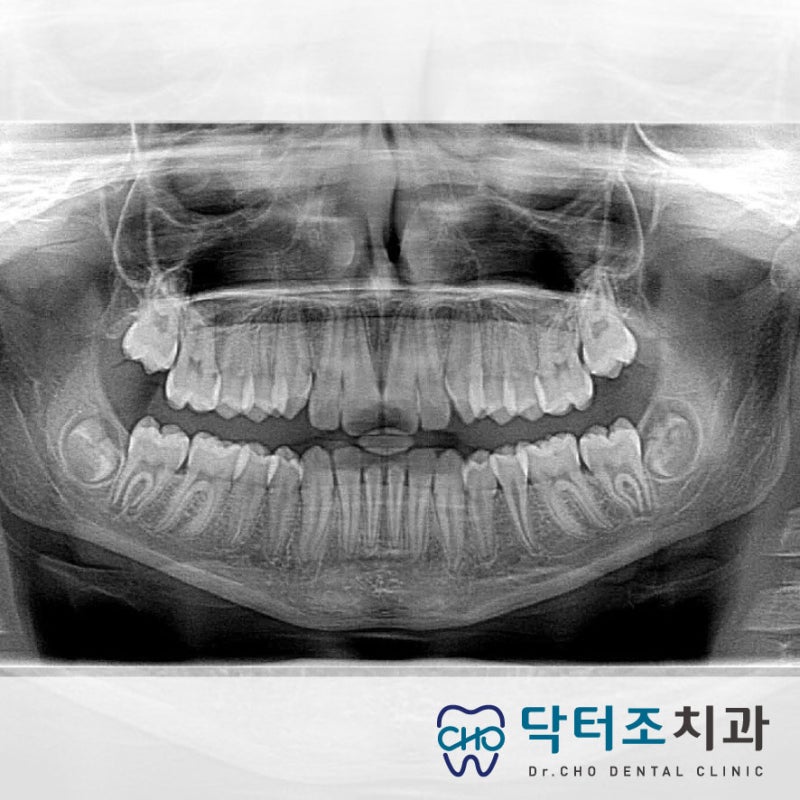

위의 엑스레이를 보면 치아 뿌리가 모여 있는 상태입니다. 그리고 치아 뿌리 쪽으로 신경관이 지나갑니다.

노란색으로 표시한 부분이 신경관입니다. 이 정도면 비교적 떨어져 있다고 생각하시면 됩니다. 다른 단면으로 보시죠.

이렇게 보면 아래턱의 신경과 뿌리가 가까워 보입니다. 위엑스레로 신경관을 그려보면